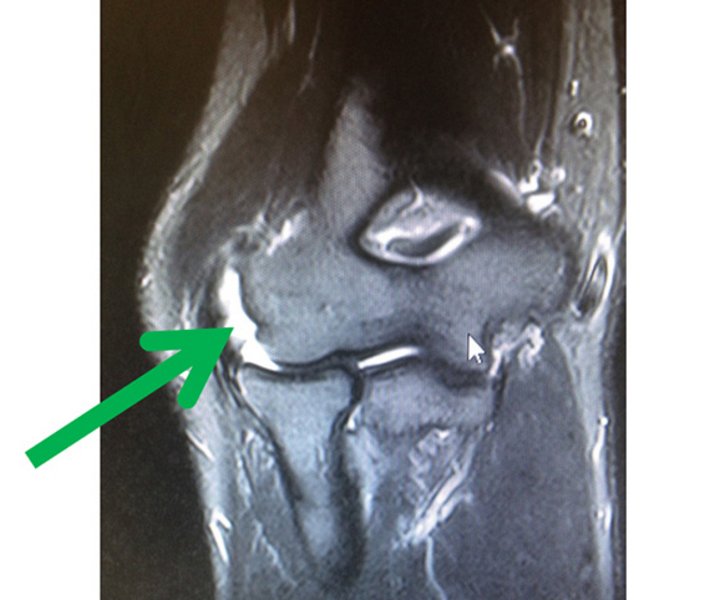

Verbleiben Schmerzen trotz einer konsequenten Therapie nach dem o.g. Schema liegt meist eine schwerere strukturelle Schädigung mit einem Sehnenanriss oder eine Instabilität vor. Dies sollte mittels eines MRTs (Kernspintomographie/ Magnetresonanztomographie) des Ellenbogens in Streckstellung untersucht werden. Je nach Ursache kann den Betroffenen meist mit einer Gelenkspiegelung und einer Befund bezogenen, minimalinvasiven Therapie (z.B. Bandplastik) geholfen werden.